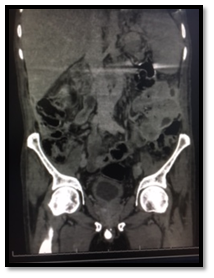

Post-operatively, The SPC was not draining well with persistent suprapubic urine leakage, so the patient was referred to our hospital 2 weeks following the primary surgery. On examination; patient was conscious, well- oriented with average general condition. Abdominal examination showed gapping of suprapubic wound with leakage of turbid urine; the SPC was not functioning well. A stone was felt in the bulbar urethra during perineal examination. Patient gave history of left nephrectomy 2 years before for a nonfunctioning kidney. Serum creatinine, BUN, HB, and WBCs were 64 mg/dl, 3.4 mmol/l , 9.9 gm, and 6640 respectively. Non- contrast CT showed no intraperitoneal fluid collection, right moderate hydroureteronephrosis, dilated left ureter with 2 stones in its lower end and 3 stones in the proximal bulbar urethra (Figure 1). Retrograde urethrocystogram showed a 3 cm stricture segment at the distal bulbar urethra and another annular stricture at the proximal bulbar urethra in addition to an urethral diverticulum in between containing the stone and grade 4 right vesico-ureteral reflux (Figure 2).

Figure 1: Non-contrast CT scan showing a big stone in the bulbar urethra and thick walled bladder.